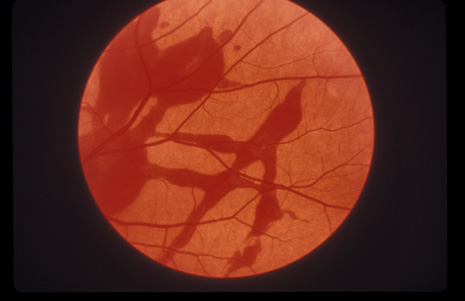

Commotio retinae (Latin, meaning retinal contusion) is a contrecoup injury. It can occur peripherally (Fig. 8) or centrally, in which case it is called Berlin's edema (Fig. 9). Immediately and for several hours after the trauma, the retina appears normal, although the patient may complain of decreased vision. Thereafter, the outer layers of affected retina become opaque. On fluorescein angiography, the opaque retina blocks background choroidal fluorescence, and in most cases there is no leakage into or under the retina (Fig. 10). For years, clinicians had difficulty explaining this blockage, because leakage is expected in conditions with edema. It was then shown in experimental animals and in human autopsy eyes that Berlin's edema is not true edema. The retinal opaqueness is the result of intracellular edema and fragmentation of the photoreceptor outer segments and intracellular edema of the underlying pigment epithelium. There is little or no intercellular fluid.66–69

Fig. 8. Peripheral commotio retinae. The retinal blood vessels are clearly seen because the retinal whitening is in the outer retinal layers.